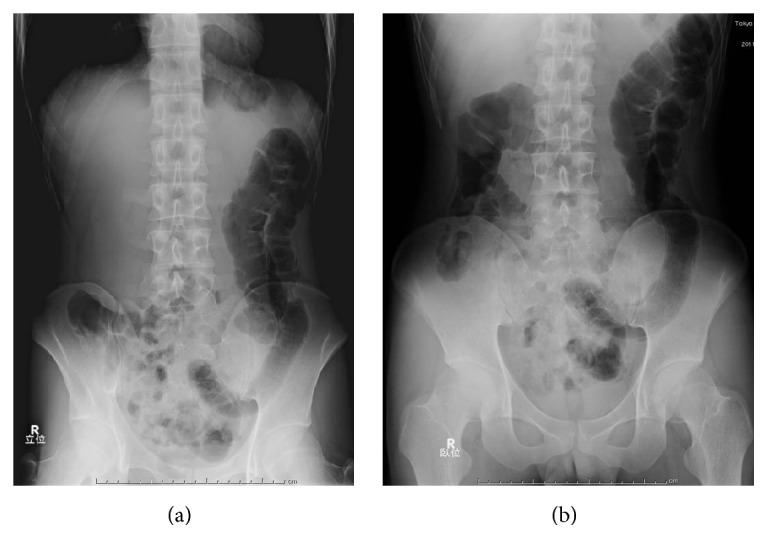

Radiologic diagnosis of colorectal foreign bodies is usually not very difficult, because inserted materials are often clearly visible on plain abdominal radiographs. However, when they are radiolucent, a plain abdominal radiograph has been reported to be useless. As radiolucent colorectal foreign bodies appear as radiolucent artificial contours or air-trapped materials in the pelvis, almost always the diagnosis itself can be made by careful evaluation of plain abdominal radiographs. We encountered a case of casting type of radiolucent colorectal foreign body formed from polyurethane foam. It presented us with unexpected radiologic findings and led to diagnostic difficulties.

结直肠异物的放射学诊断通常不是很困难,因为插入的异物在腹部平片上往往清晰可见。然而,当异物为透射线时,据报道腹部平片并无诊断价值。由于透射线的结直肠异物在骨盆中表现为透射线的人工轮廓或气体包裹物,几乎总是可以通过仔细评估腹部平片来做出诊断。我们遇到一例由聚氨酯泡沫形成的铸型透射线结直肠异物病例。它给我们带来了意想不到的放射学表现,并导致了诊断困难。